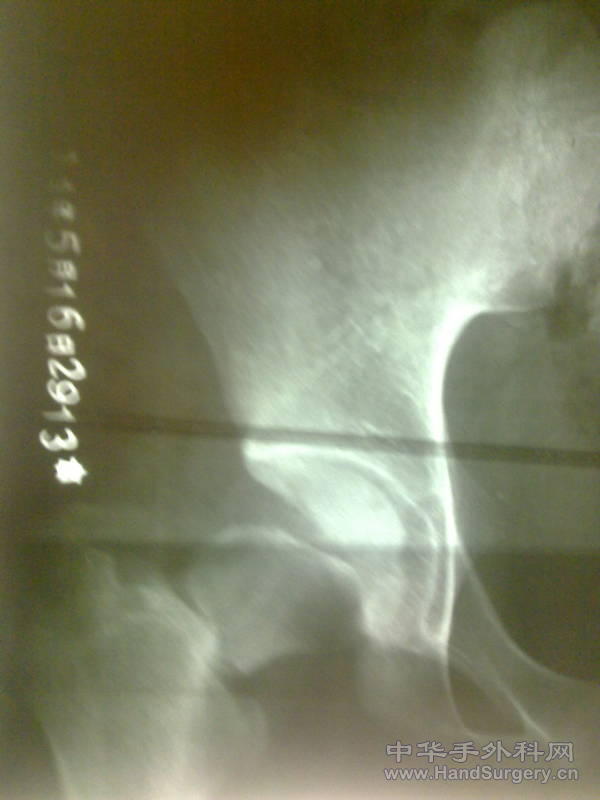

发一例股骨颈骨折

患者17岁,外伤致股骨颈骨折,请大家看看是否有更好的固定方法。